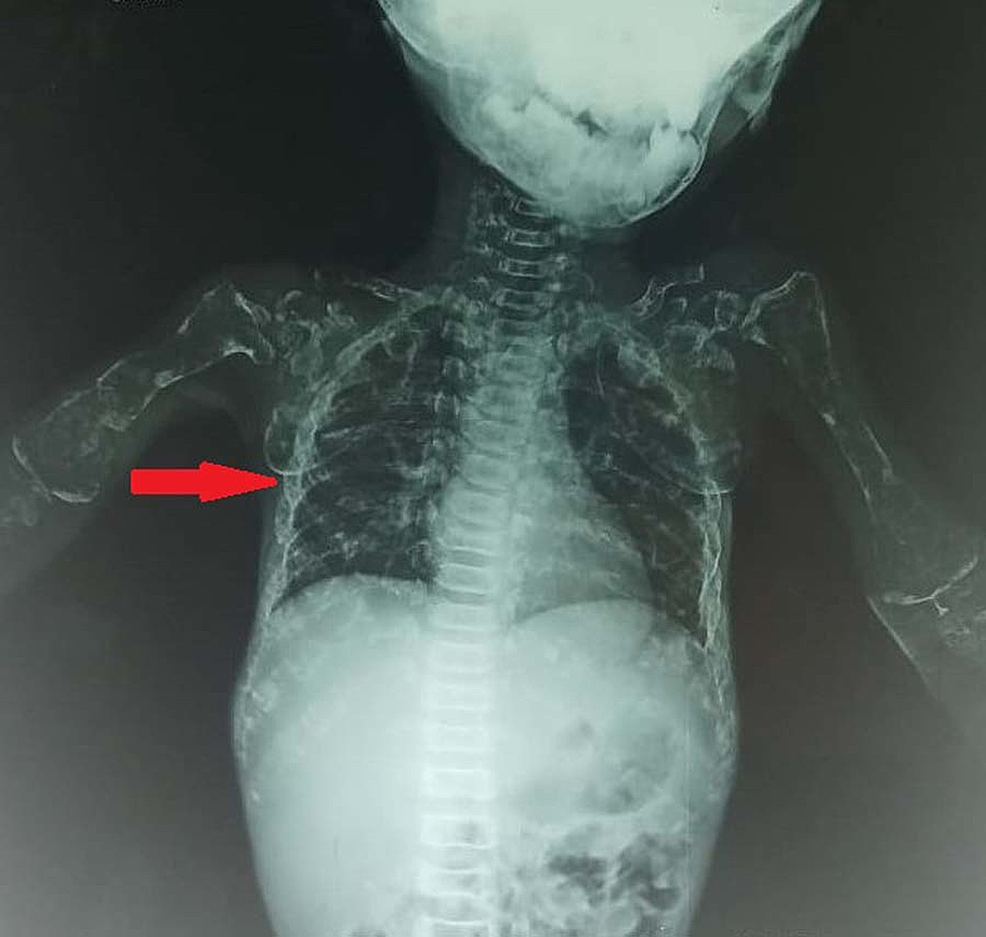

From www.pinterest.com

Rib Fracture, Fractures, Medical Imaging, Radiology, Pediatrics, Case Rib Fracture Kidney Damage Fractures of the posterior portion of the lower ribs can be associated with kidney injury. Mineral and bone disease is omnipresent in patients with chronic kidney disease (ckd) and leads to a diverse range of clinical manifestations, including bone. If you break a rib toward the bottom of your rib cage, the sharp end of the bone could cause damage. Rib Fracture Kidney Damage.